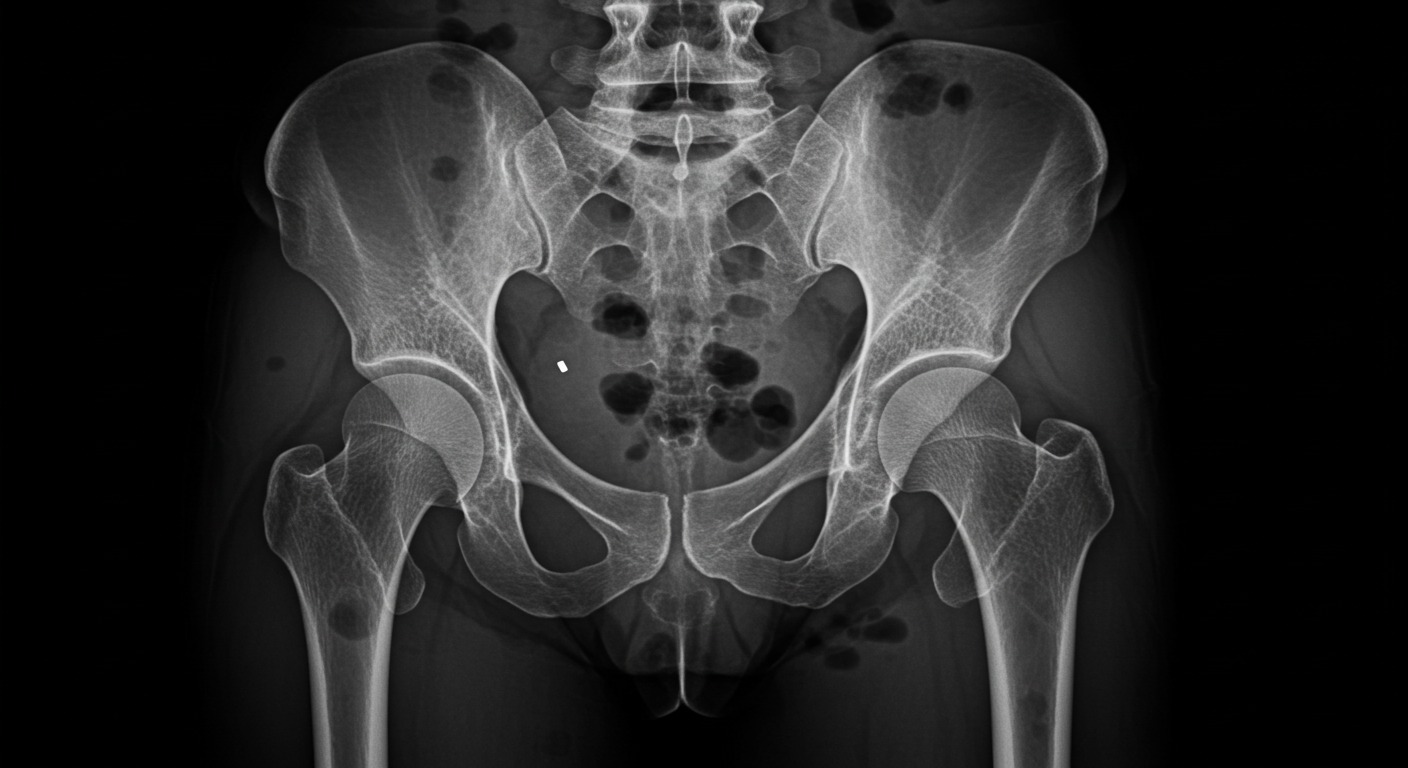

- Method: Bone mineral density measured using DEXA (spine L2–L4 and total femur)

- Femur BMD and T-score: No significant difference